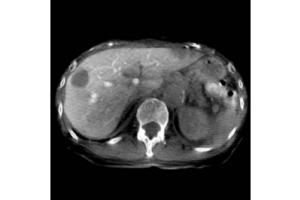

- Лучевая диагностика

Визуализация Shimadzu